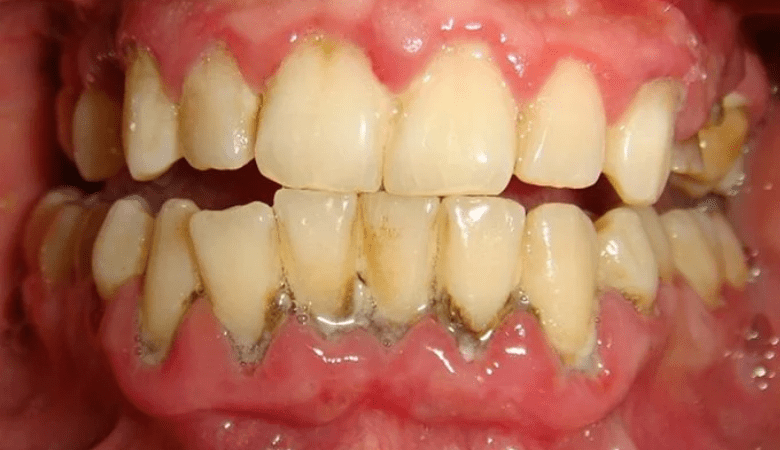

Viêm nướu răng chuyển biến nặng (Nguồn: Internet)

Viêm nướu răng ở mức độ nặng (Nguồn: Internet)

Quá nhiều cao răng lâu ngày gây viêm nướu răng (Nguồn: Internet)

- Nướu sưng tấy và phồng lên: Nướu có biểu hiện sưng, căng bất thường.

- Thay đổi màu sắc nướu: Nướu chuyển sang màu đỏ hoặc hồng đậm hơn so với trạng thái khỏe mạnh.